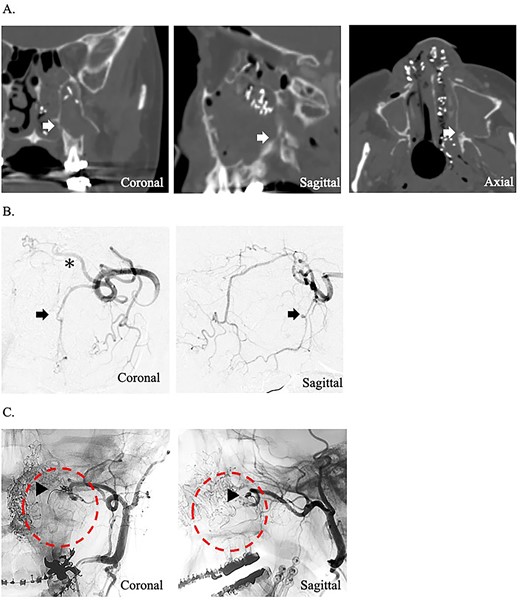

A 49-year-old woman with severe hemorrhage after Le Fort I maxillary osteotomy and sagittal split ramus osteotomy was transferred to our hospital. She underwent surgery for a jaw deformity 7 days earlier by the dentist at another hospital, and postoperative Day 5, severe epistaxis from the left nasal cavity occurred. At the previous hospital, the patient was treated for epistaxis by nasal tampons; however, the hemorrhage could not be completely stopped. After transport, an endoscope was used to search for the bleeding point from the left nasal cavity. The source of hemorrhage was identified near the natural ostium of the maxillary sinus. This massive was impossible to control under endoscopy; therefore, temporary hemostasis was used with nasal packing. Contrast-enhanced computed tomography of the paranasal area revealed that the maxilla and the pterygoid fragment were cut and separated. A cut of the bone was also found around the descending palatine artery, and blood was found within the maxillary sinus (Fig. 1A). The preoperative hemoglobin concentration was 12.6 g/dL, and the hematocrit was 38.0%. After transport, hemoglobin concentration slightly decreased to 11.2 g/dL and hematocrit to 34.6%. Since the bleeding point could not be identified by endoscopy and the hemorrhage continued, an angiographic embolization by a radiologist was selected as the hemostatic method. The angiography showed a pseudoaneurysm of the left descending palatine artery, on which embolization was performed by endovascular coils and gelatin sponges (Fig. 1B and C). Although hemostasis was achieved adequately after angiographic embolization, the hemoglobin concentration and hematocrit were further decreased to 9.8 g/dL and 30.0%, respectively.

(A) Postoperative coronal, sagittal, and axial computed tomography images, which show the separated bone parts of the left maxilla (arrow). (B) Coronal and sagittal selective angiographic images from the left internal maxillary artery. The arrow indicated a pseudoaneurysm of the left descending palatine artery. The asterisk indicated the left sphenopalatine artery. (C) After embolization and coronal and sagittal selective angiographic images. The Triangular arrow indicated the endovascular coils, and the circle indicated the disappearance of the vascular flow area.